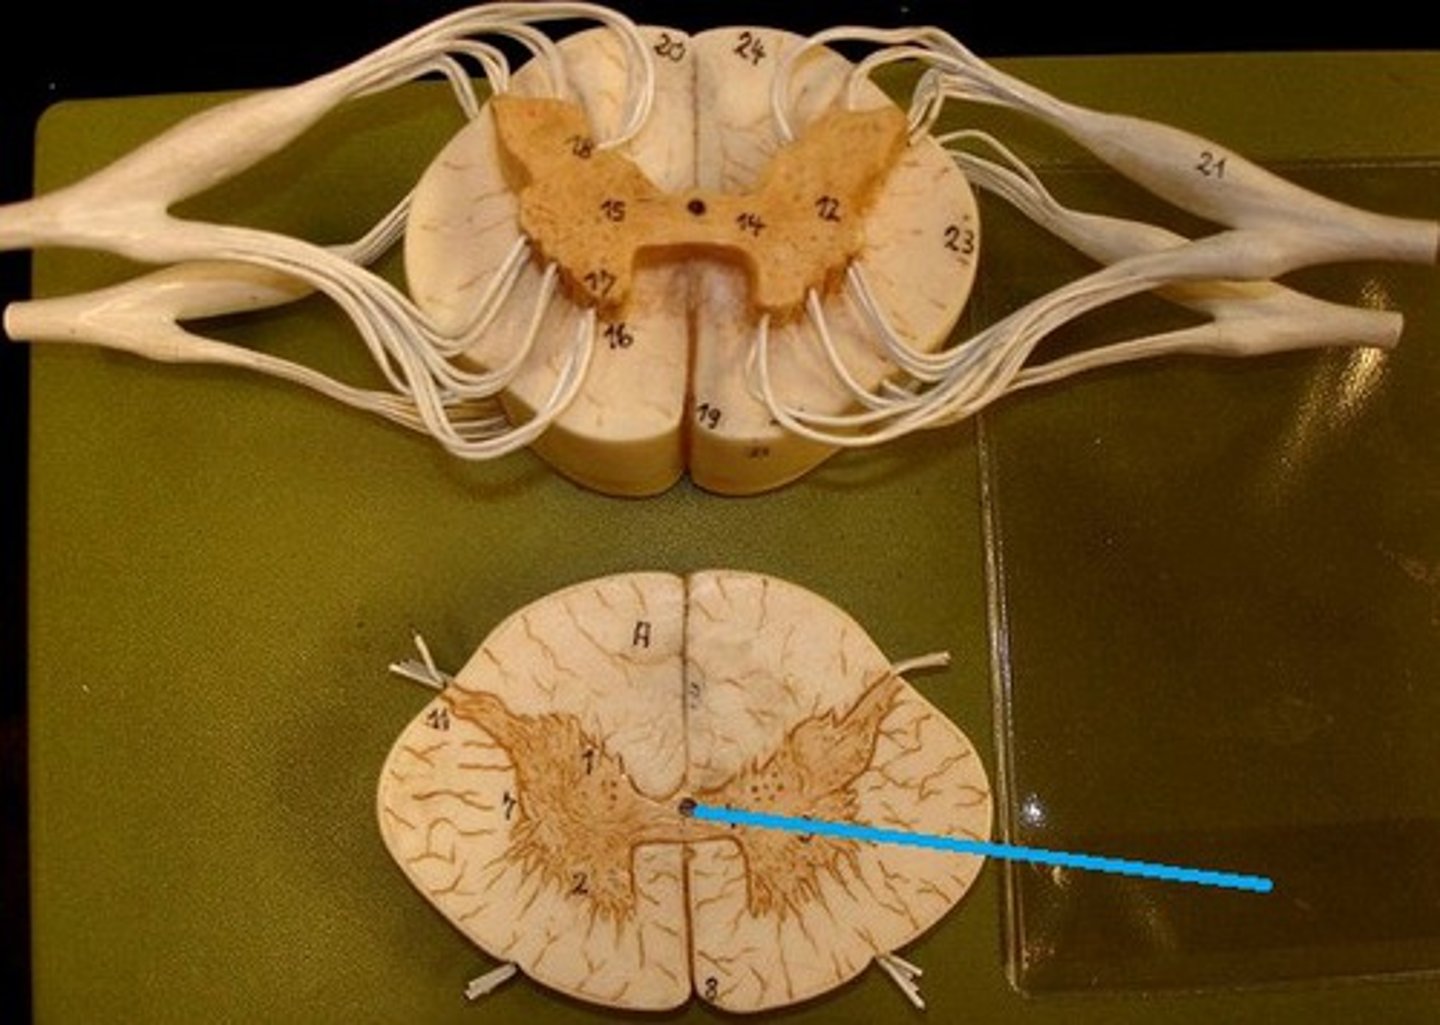

Spinal cross section (1)

Spinal cross section (2)

dorsal horn of spinal cord

cell bodies synapsed by afferent neurons (sensory)

ventral horn of spinal cord

The upper motor neurons that control the skeletal muscles are found in

lateral horn of spinal cord

Contains the cell bodies of the preganglionic ANS neurons

dorsal column

a white matter tract on the dorsal side of the spinal cord, carrying fine touch and proprioceptive axons to the brain stem

spinothalamic tract

pain and temperature

corticospinal tract

What tract is responsible for voluntary refined movements of distal extremities?

dorsal rootlets

ventral rootlets

spinal nerves

central canal of spinal cord

ventral white comissure

Dorsal Root Ganglion (DRG)

associated with the dorsal horns; cell bodies of sensory neurons are located here